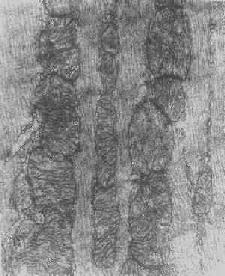

图1-8 心肌细胞线粒体 ×16000

图1-9 线粒体肿

图1-10肾小管上皮细胞线粒体部分空泡变 ×20000

图1-11 线粒体肿胀(基质型)空泡变(心肌缺氧) ×8400